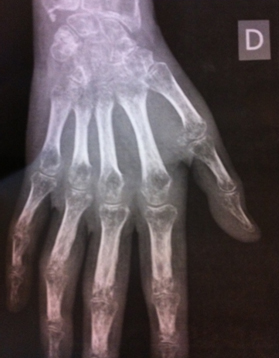

Mme F., 48 ans, a présenté un cancer du sein droit en 2008. Elle a été opérée avec ablation du sein et curage ganglionnaire. Depuis, elle va très bien.

Elle a fait une chute de vélo début novembre 2012 et a présenté une fracture de l’extrémité inférieure du radius droit. Elle a été opérée avec 3 broches et plâtrée pendant 3 semaines. Deux broches ont été enlevées sans anesthésie, la troisième a nécessité une courte AG.

Quinze jours après, elle a présenté une inflammation très impressionnante de la main et